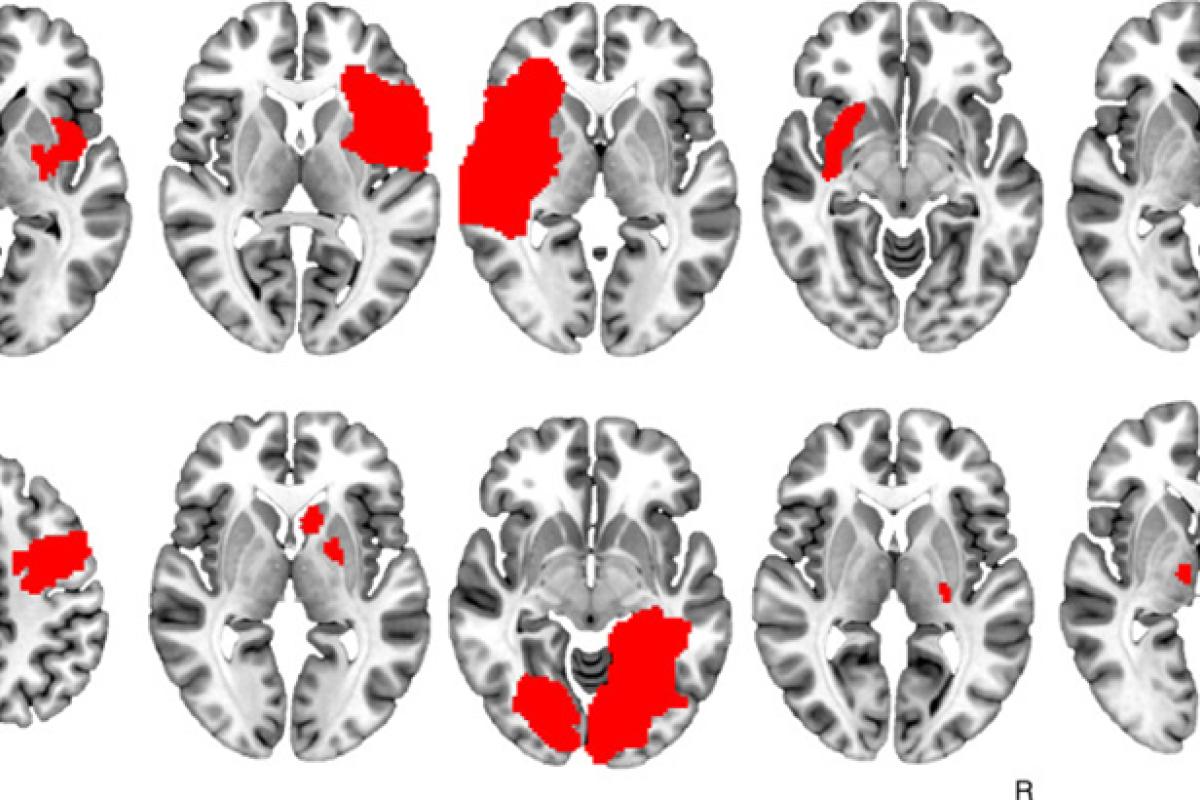

Dr. Jordan Grafman Co-Authors Study on Link Between Brain Lesions and Addiction